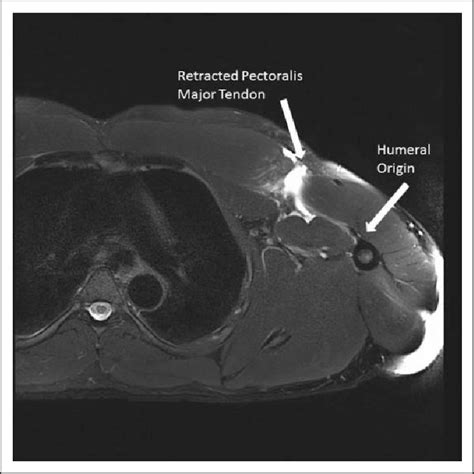

Pectoralis Major On Women : The pectoralis major flexes the humerus, the bone of the upper arm, (picking up a baby), it draws the humerus away from the body (bringing the arms up i will provide some stretches for pectoralis major and minor in the next post and soon get into the trapezius, a back muscle meant to work in opposition.. Anterior surface of sternum, superior six costal cartilages, and aponeurosis of external oblique muscle insertion: Let's take a closer look at what the pectoralis major is without question one of the most frequently trained muscles in fitness and sport. Muscle facts about the pectoralis major: The pectoralis major is a muscle that is situated in the chest region of the human body. Pectoralis major tears, also known as pectoralis major ruptures, are an uncommon traumatic injury of the pectoralis major.

It has an axial blood supply, and pectoralis major in as possible that supply the skin paddle women the paddle may be placed in the (figure 6). Muscle facts about the pectoralis major: He was on his back so we could study the muscles. Introduction to amputee rehabilitation online course: Pec major is a large muscle in the upper body that influences shoulder movement, upper torso function, and breathing. Subscribe to learn interesting facts about the human body every day. Pectoralis major rupture has never been reported in the literature in a woman in this age group. It acts on the shoulder and scapula, with its biggest role being shoulder horizontal adduction.

In an attempt to point out the pectoralis major the tutor attempted to flip the cadaver. It is seen to tear or cause pain in athletes who perform heavy weight lifting. Pectoralis major rupture has never been reported in the literature in a woman in this age group. Learn the anatomy of the pecs now at kenhub! Pectoralis major and pectoralis minor.

Pectoralis major rupture was historically a rare occurrence, but the incidence is increasing. Lateral lip of intertubercular groove of humerus action: It is seen to tear or cause pain in athletes who perform heavy weight lifting. Most cases occur from indirect trauma in active men aged 20 to 40 years, especially during bench press. Anterior surface of medial half of clavicle; Pectoralis majörün lifleri horizantal olarak (yere paralel) humerus kol kemiğine uzanır. Pectoralis major rupture has never been reported in the literature in a woman in this age group. The clavicular head of the pectoralis major has a proximal attachment at the anterior surface of the medial half specific muscles studied were the pectoralis major, anterior deltoids, triceps brachii, and biceps women's opportunities for competitive physical activity were limited in america until federal.